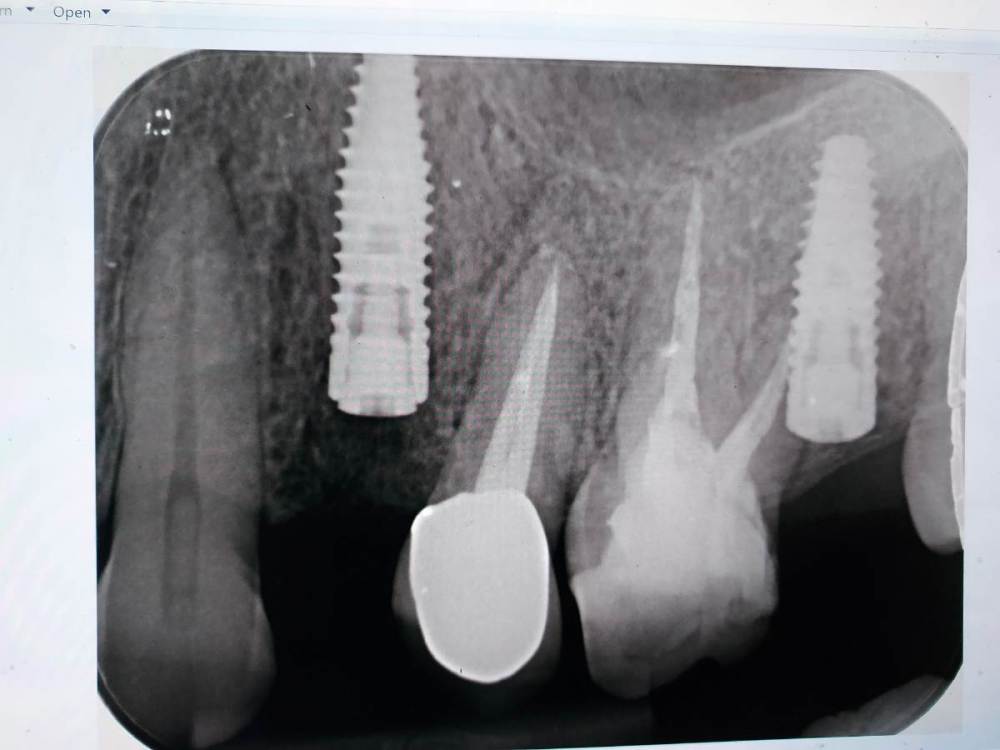

lola-1234 Опубликовано 29 октября, 2021 Автор Поделиться Опубликовано 29 октября, 2021 (изменено) 23 часа назад, Irouil сказал: Я не могу сказать что пошло не так, ситуация действительно не очевидная покажите снимок, который Вы упомянули в предыдущем сообщении Да вот тот же снимок, новый пока не делали. P.S. Спасибо Irouil, что поделились своими мыслями Изменено 29 октября, 2021 пользователем lola-1234 Ссылка на комментарий

Irouil Опубликовано 8 декабря, 2021 Поделиться Опубликовано 8 декабря, 2021 А имплант Ваш точно интегрирован? Не хочется искать чёрную кошку в темной комнате, но этот снимок нравится мне меньше предыдущих Ссылка на комментарий

Irouil Опубликовано 13 декабря, 2021 Поделиться Опубликовано 13 декабря, 2021 (изменено) @lola-1234 Я хочу сказать, что Ваш снимок (последний) выглядит неоднозначно. Есть выраженная радиопрозрачность (потемнение на снимке) между зубом и имплантом, что может говорить о его «неполной» интеграции. Проверить это можно только так, как описывает @Bier - попробовать его выкрутить с определенным усилием. Если имплант его не выдерживает, то спасать там нечего - он все равно Вас подведёт, лучше раньше, чем позже. Очень часто врачи не проверяют интеграцию имплантов инструментально (так, как описано выше) и очень редко, но могут быть ложно-отрицательные результаты - имплант вроде стоит крепко, не шатается, но после протезирования через короткое время подводит. Именно поэтому мы тут обсуждаем эту важную, но очень маленькую деталь - проверку «торком». Тем не менее, на этом же снимке вдоль шейки зуба со стороны импланта видна костная ткань, что может говорить о простом артефакте снимка в том месте, которое выглядит как «отошедшая кость» - возможно, что и имплант интегрирован, и все вообще там здорово. Тогда нужно будет его протезировать, смысла удалять его уже не будет, скорее всего он проблем не вызывает. Но, в такой ситуации, до протезирования я бы сходил на Вашем месте к неврологу и поискал бы вместе с доктором причину болей. Изменено 13 декабря, 2021 пользователем Irouil 1 Ссылка на комментарий